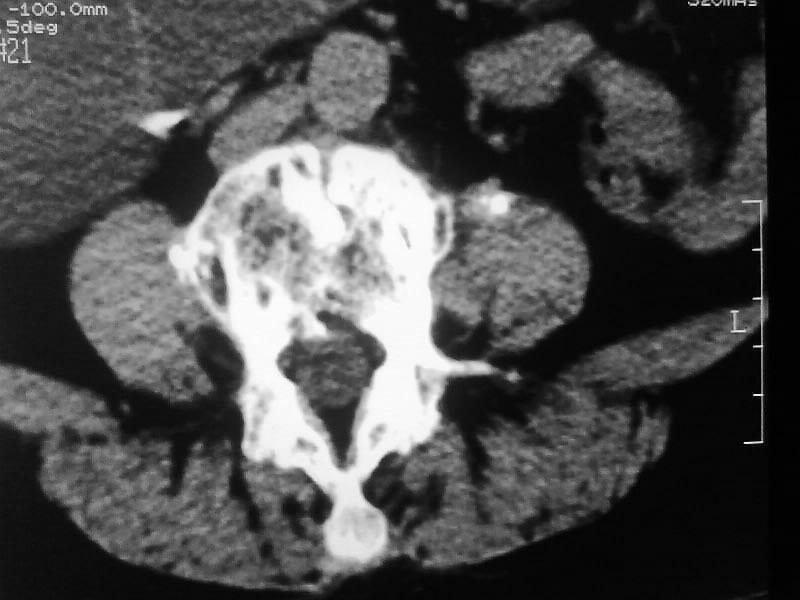

定位相示l2呈楔形改变(ct示陈旧性骨折改变,图像未传),l4.5椎体融合,以下是l4.5ct平扫.请各位看看,

考虑结核(有破坏、硬化及死骨)。

1、三四椎体结核,2、水平骶椎。

1、l1压缩性骨折(陈旧性)。

2、l3、4椎体结核。

就是腰1压缩性骨折,腰3\\4椎体结核(融合),水平骶椎.

支持 l1椎体陈旧性压缩性骨折;l3、4椎体结核(融合);水平骶椎。